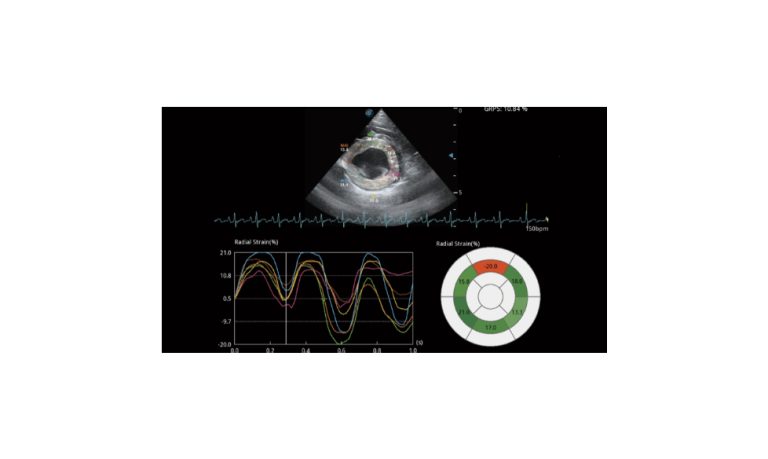

SonoScape Pro Pet E11

Smart Imaging

Introducing the first portable ultrasound with the C-Field+TM platform, redefining diagnostic imaging. Designed for veterinarians, it delivers unmatched clarity, ultra-fast processing, and seamless adaptability for all species. Experience Smart Imaging, Heartfelt Care—anywhere.

Equipped with cutting-edge veterinary software and optimized workflows, it embodies our commitment to Smart Imaging, Heartfelt Care – Wherever Their Journey Leads, with unparalleled performance and adaptability, this innovative system empowers veterinarians to provide exceptional care across all diagnostic applications,